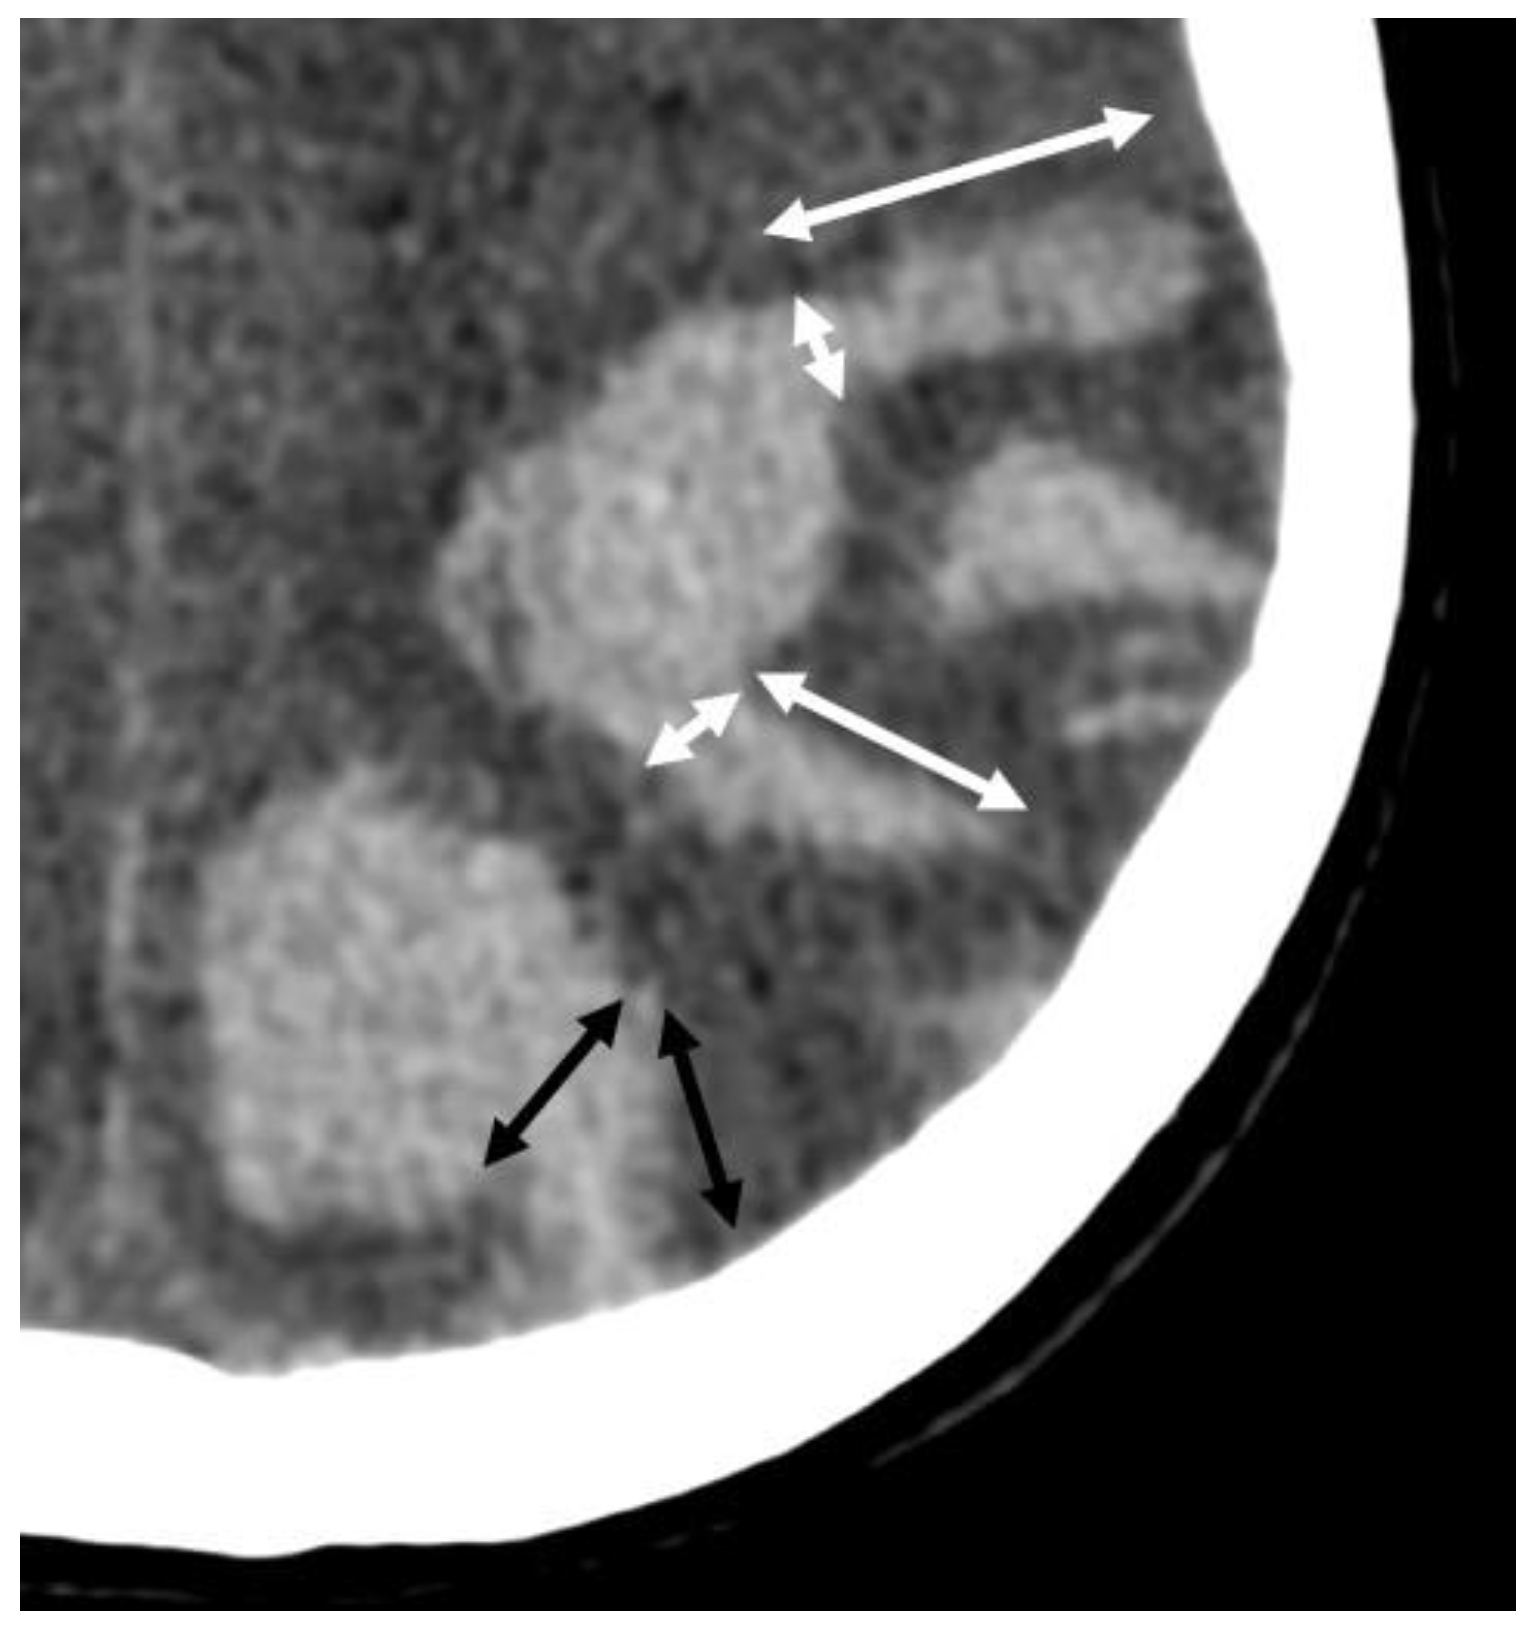

- Rodrigues, M.A.; Samarasekera, N.; Lerpiniere, C.; Humphreys, C.; McCarron, M.O.; White, P.M.; Nicoll, J.A.R.; Sudlow, C.L.M.; Cordonnier, C.; Wardlaw, J.M.; et al. The Edinburgh CT and genetic diagnostic criteria for lobar intracerebral haemorrhage associated with cerebral amyloid angiopathy: Model development and diagnostic test accuracy study. Lancet Neurol. 2018, 17, 232–240. [Google Scholar] [CrossRef]